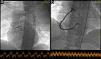

The coronary angiogram showed simultaneous acute thrombosis of the right coronary artery (RCA) (Figure 2a) and of the left anterior descending (LAD) artery (Figure 3a). Initially, to visualize suspected plaque rupture and to aid the decision whether to implant stents, multiple aspiration thrombectomies were performed, resulting in removal of substantial amounts of thrombotic material (Figure 4). After intravenous and intracoronary administration of abciximab, an everolimus-eluting stent was implanted into the RCA, restoring good epicardial coronary flow (Figure 2b). In the LAD spontaneous reperfusion occurred, revealing a massive thrombus (Figure 3b). After aspiration thrombectomy, a stent was implanted (Figure 3c). Echocardiographic examination revealed inferior wall and basal septal akinesis with ejection fraction of 35%. Right ventricular enlargement (5.4 cm in apical 4-chamber view) and hypokinesis (tricuspid annular plane systolic excursion [TAPSE] 14 mm) were present. Right ventricular function was improved on control echocardiography (TAPSE 27 mm).